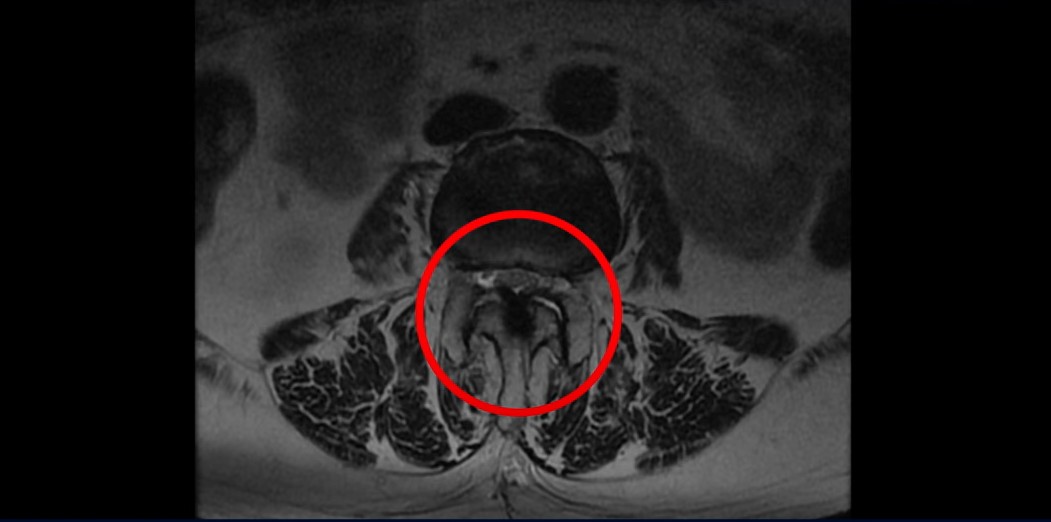

이 환자분은 협착증 수술 예약을 날짜까지 잡아놓고 넘어지면서 압박골절이 발생하고 협착증 증상 즉, 골반과 다리증상이 심하게 악화됩니다. 이분 MRI를 보시면 척추 2번 뼈에는 넘어지면서 생긴 척추압박골절이 보입니다.

3번과 4번 마디에는 황색인대 골화증으로 인한 중심성 협착이 보입니다.

4번과 5번 마디는 전방전위증이 있고 15년 전 허리수술을 받은 적이 있어서 척추 후관절과 후궁을 제거한 흔적들이 보입니다.

또 5번 1번에는 왼쪽 신경가지가 빠져나가는 추간공 즉 신경구멍이 많이 좁아져 있습니다. 이 환자분은 허리통증과 함께 왼쪽 다리 증상이 심하셨는데 이것 때문인 것으로 보입니다.